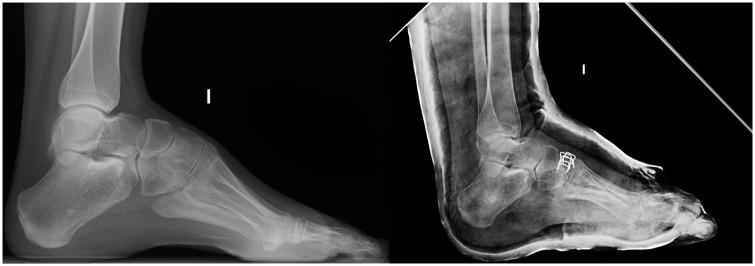

如何治疗儿童及青少年高弓足?

How to manage pes cavus in children and adolescents?

Pes cavus in its different forms is not a pathological entity, but rather the manifestation of multiple diseases.Cavovarus, a form of cavus foot, should never be considered a physiological deformity. A neurological condition should always be excluded.The evolution of pes cavovarus is unpredictable because of the large number of conditions involved in its aetiology, as well as their variable degree of expression. About 66% of cavovarus feet are the result of subtle neurological diseases, which only become evident later in life.Although surgery may not change quality of life, recent studies suggest that it may improve foot posture and reduce walking instability.The aim of treatment is to preserve a painless, plantigrade, mobile foot. Management consists of correcting bone deformity while preserving movement, and the wise use of rebalancing techniques. Arthrodesis should only be a salvage procedure. Cite this article: 2021;6:510-517. DOI: 10.1302/2058-5241.6.210021.

不同形式的高弓足并非一种病理实体,而是多种疾病的表现。高弓内翻足作为高弓足的一种形式,绝不应被视为生理性畸形。必须始终排除神经疾病。由于高弓内翻足病因涉及多种情况及其不同程度的表现,其演变不可预测。约66%的高弓内翻足是由细微的神经疾病导致的,这些疾病在生命后期才会显现出来。尽管手术可能不会改变生活质量,但最近的研究表明,手术可能会改善足部姿势并减少行走不稳。治疗的目的是保持无痛、足底着地、可活动的足部。治疗包括在保留活动能力的同时纠正骨骼畸形,并明智地运用重新平衡技术。关节融合术应仅作为一种挽救性手术。引用本文:2021;6:510 - 517。DOI: 10.1302/2058 - 5241.6.210021。